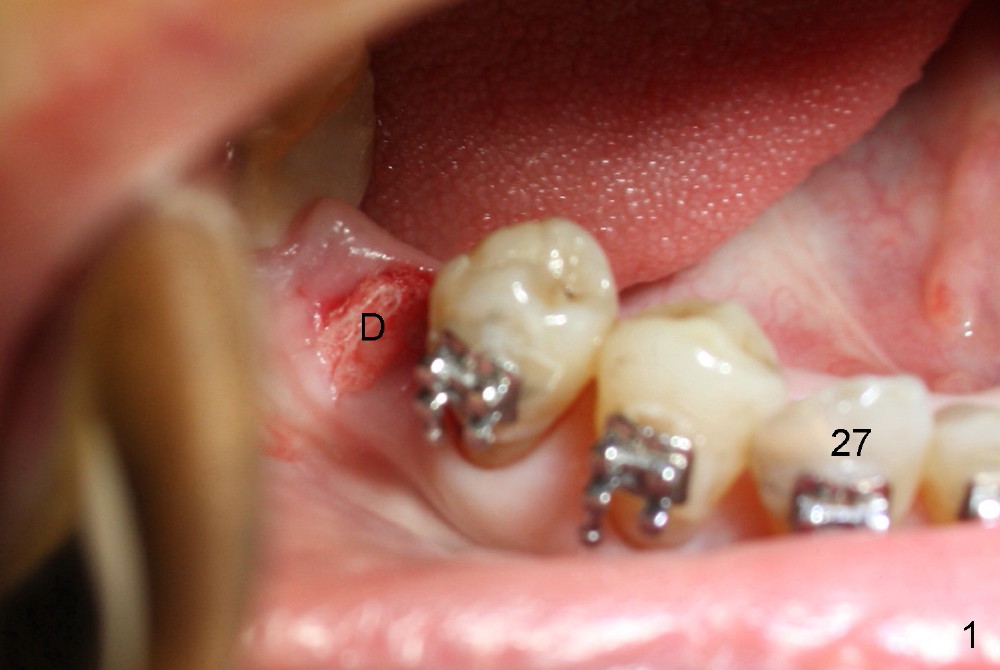

The malpositioned #29 was distalized using #32 as an anchorage. Crowding exists around #27 (Fig.1). To distalize #28 and 29 more effectively, an implant is placed at the distal socket of #30 (Fig.1 D; Fig.2).

An abutment is placed; a provisional is fabricated, a premolar band is tried in and cemented (Fig.4: #30). Next visit, the implant will be used as an anchorage to distalize #29 and 28 (arrow) so that there is enough space to restore the distal defect of #27 (*).